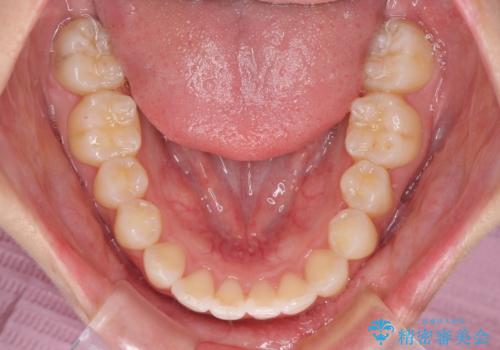

骨格的な左右差があったため、上下の正中を合わせることは困難かと思われましたが、何とか合わせることができました。

一方、骨格の差は改善できないため、奥歯の咬み合わせに物足りなさを感じました。

奥歯の咬み合わせによる不自由はなく、患者様に大変満足していただきました。